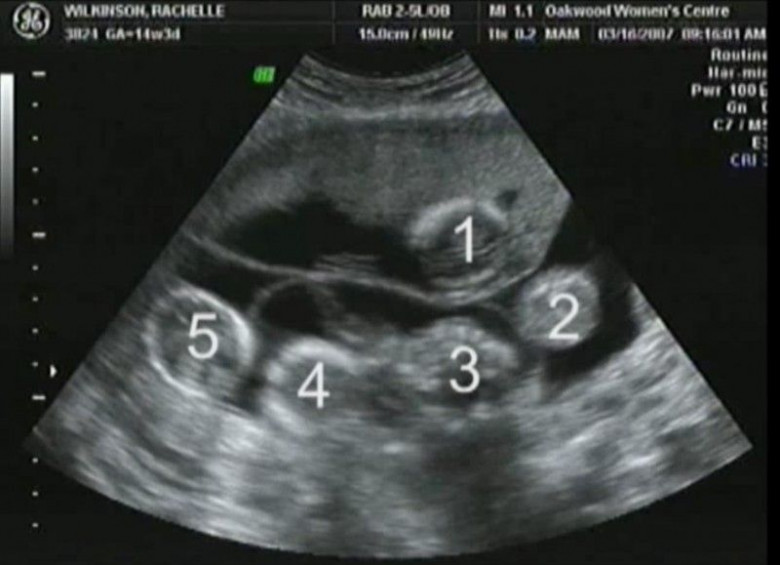

Բայց այսքանով պատմությունը չի վերջանում։ Երբ հաջորդ անգամ բժիշկը ՈՒՁՀ էր անցկացնում, Ռեյչլը չէր կարողանում հավատալ իր աչքերին. սրտի բաբախյունները երկուսը չէին ու նույնիսկ երեքն էլ չէին։ Բժիշկը հաշվեց 5 երեխա։

Ամուսինները պարզապես շշմած էին։ Բազմապտուղ հղիությունը հազվադեպ է պատահում, բայց երբեմն լինում է այդպես անպտղության դեմ բուժման արդյունքում։ Նրանք դժվար ընտրության առաջ էին կանգնած։ Բժիշկների կանխատեսումները լավատեսական չէին. հղիությունը բարդ էր լինելու, ու պարզ չէր, կապրեն արդյո՞ք բոլոր 5 երեխաները։ Բայց նրանք որոշեցին պահել հինգին է։